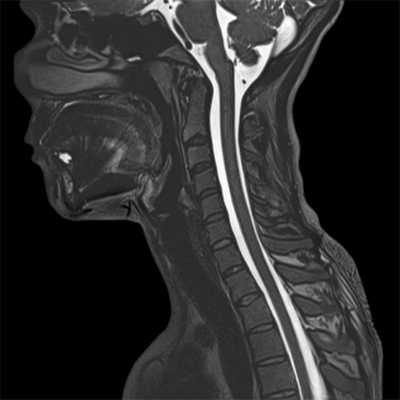

МРТ шеи: оценка спинного мозга (сагиттальная плоскость, Т2 последовательность)

МРТ шейного отдела позвоночника - высокоинформативный неинвазивный способ диагностики, использующий магнитное поле и компьютерную обработку для получения изображений. Преимущества магнитно-резонансного сканирования в сравнении с рентгеновскими методами обследования - отсутствие лучевого воздействия и возможность детализации патологических процессов в мягких тканях: на томограммах видны хрящи, синовии, связки, межпозвонковые диски, спинной мозг, нервы. Если в организме человека нет металлических составляющих или функционирующих устройств с ферромагнитными свойствами, негативные последствия, включая отдаленные, после проведения диагностической процедуры отсутствуют.

МРТ шейного отдела позвоночника: оценка лордоза, сагиттальная плоскость, Т2 последовательность